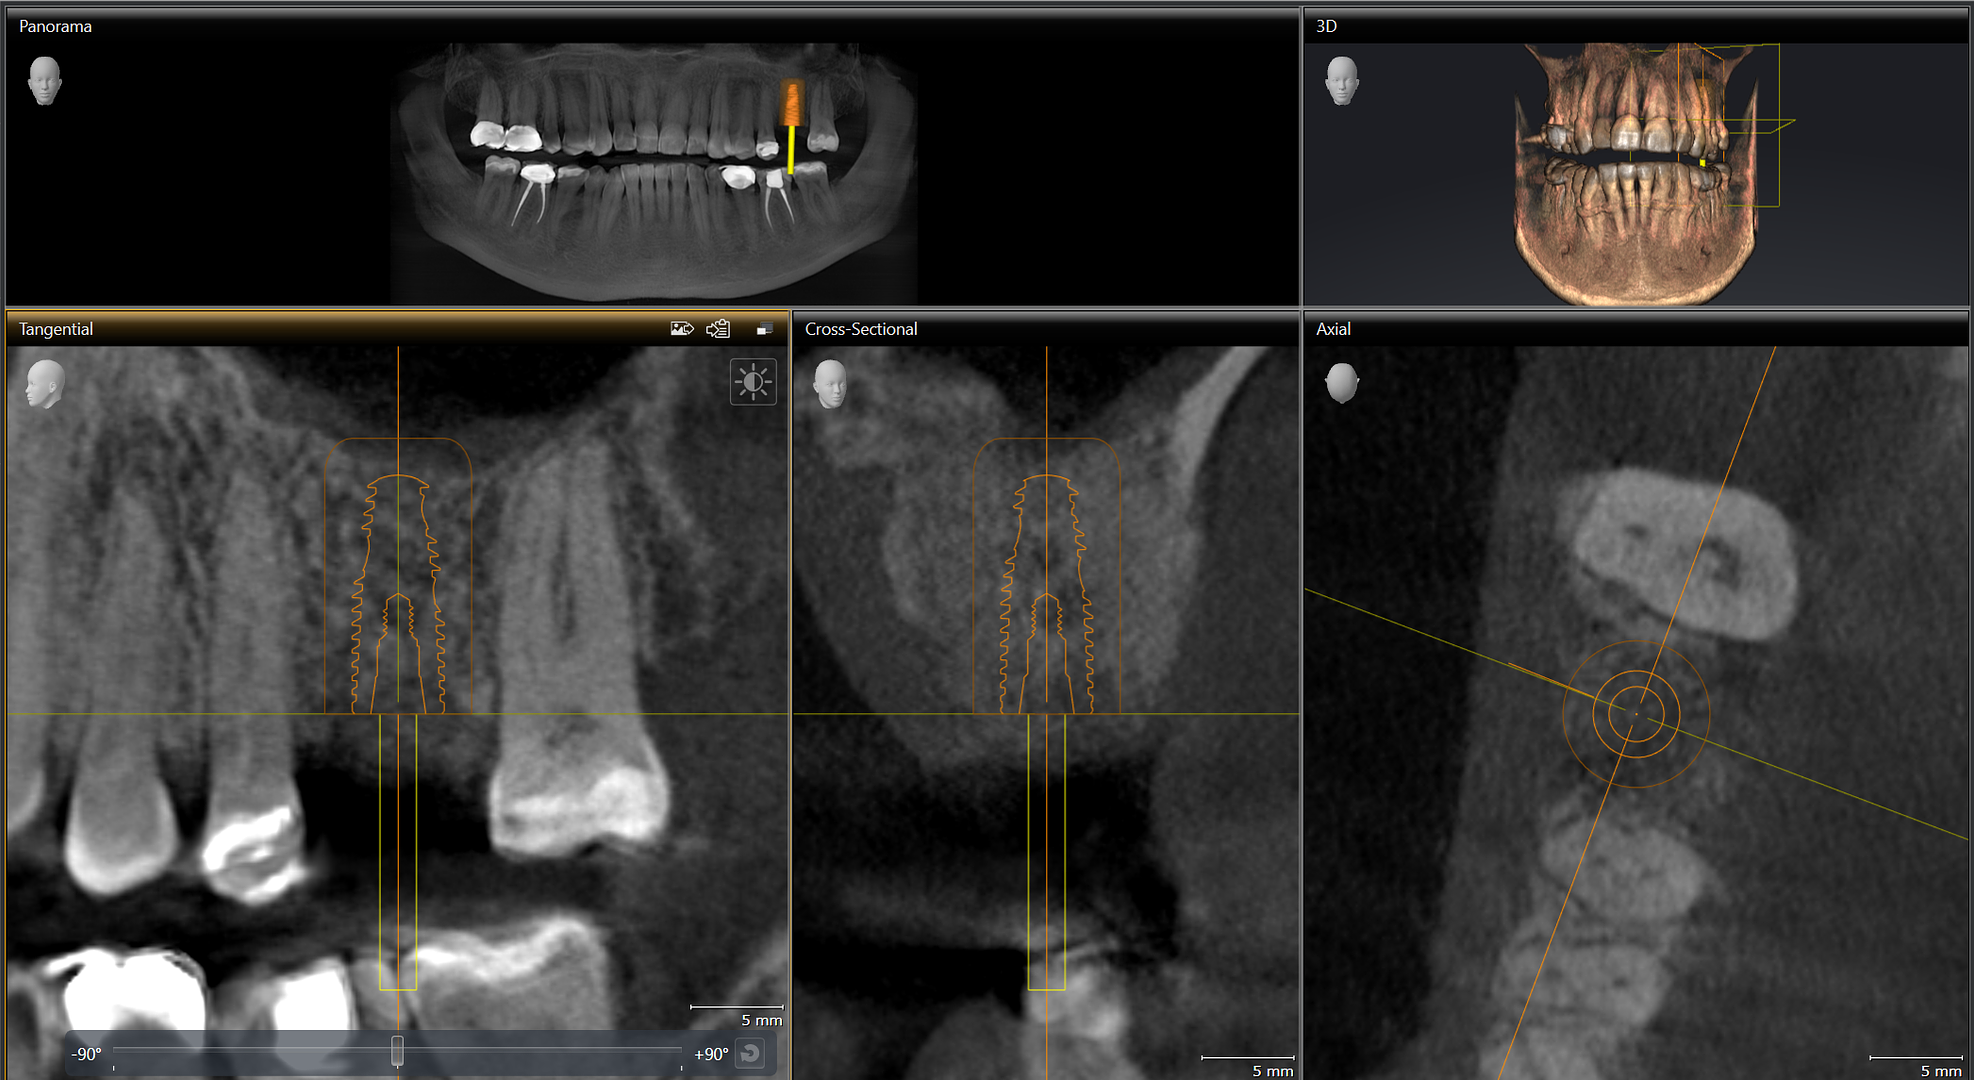

Implant of the Day with Dr. Rick Sullivan

62 year old male reported last year with discomfort on the maxillary left molar region. PA x-ray showed some lesions and because we take a cone beam on everyone, we were able to see massive bone loss around all three roots that extended up into and around the sinus floor. Patient chose to have a […]